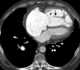

Chronic left ventricular failure

Heart failure (HF), also known as congestive heart failure (CHF), decompensatio cordis (DC), and congestive cardiac failure (CCF), is when the heart is unable to pump sufficiently to maintain blood flow to meet the body tissue's needs for metabolism. Signs and symptoms of heart failure commonly include shortness of breath, excessive tiredness, and leg swelling. [Source: Wikipedia ]